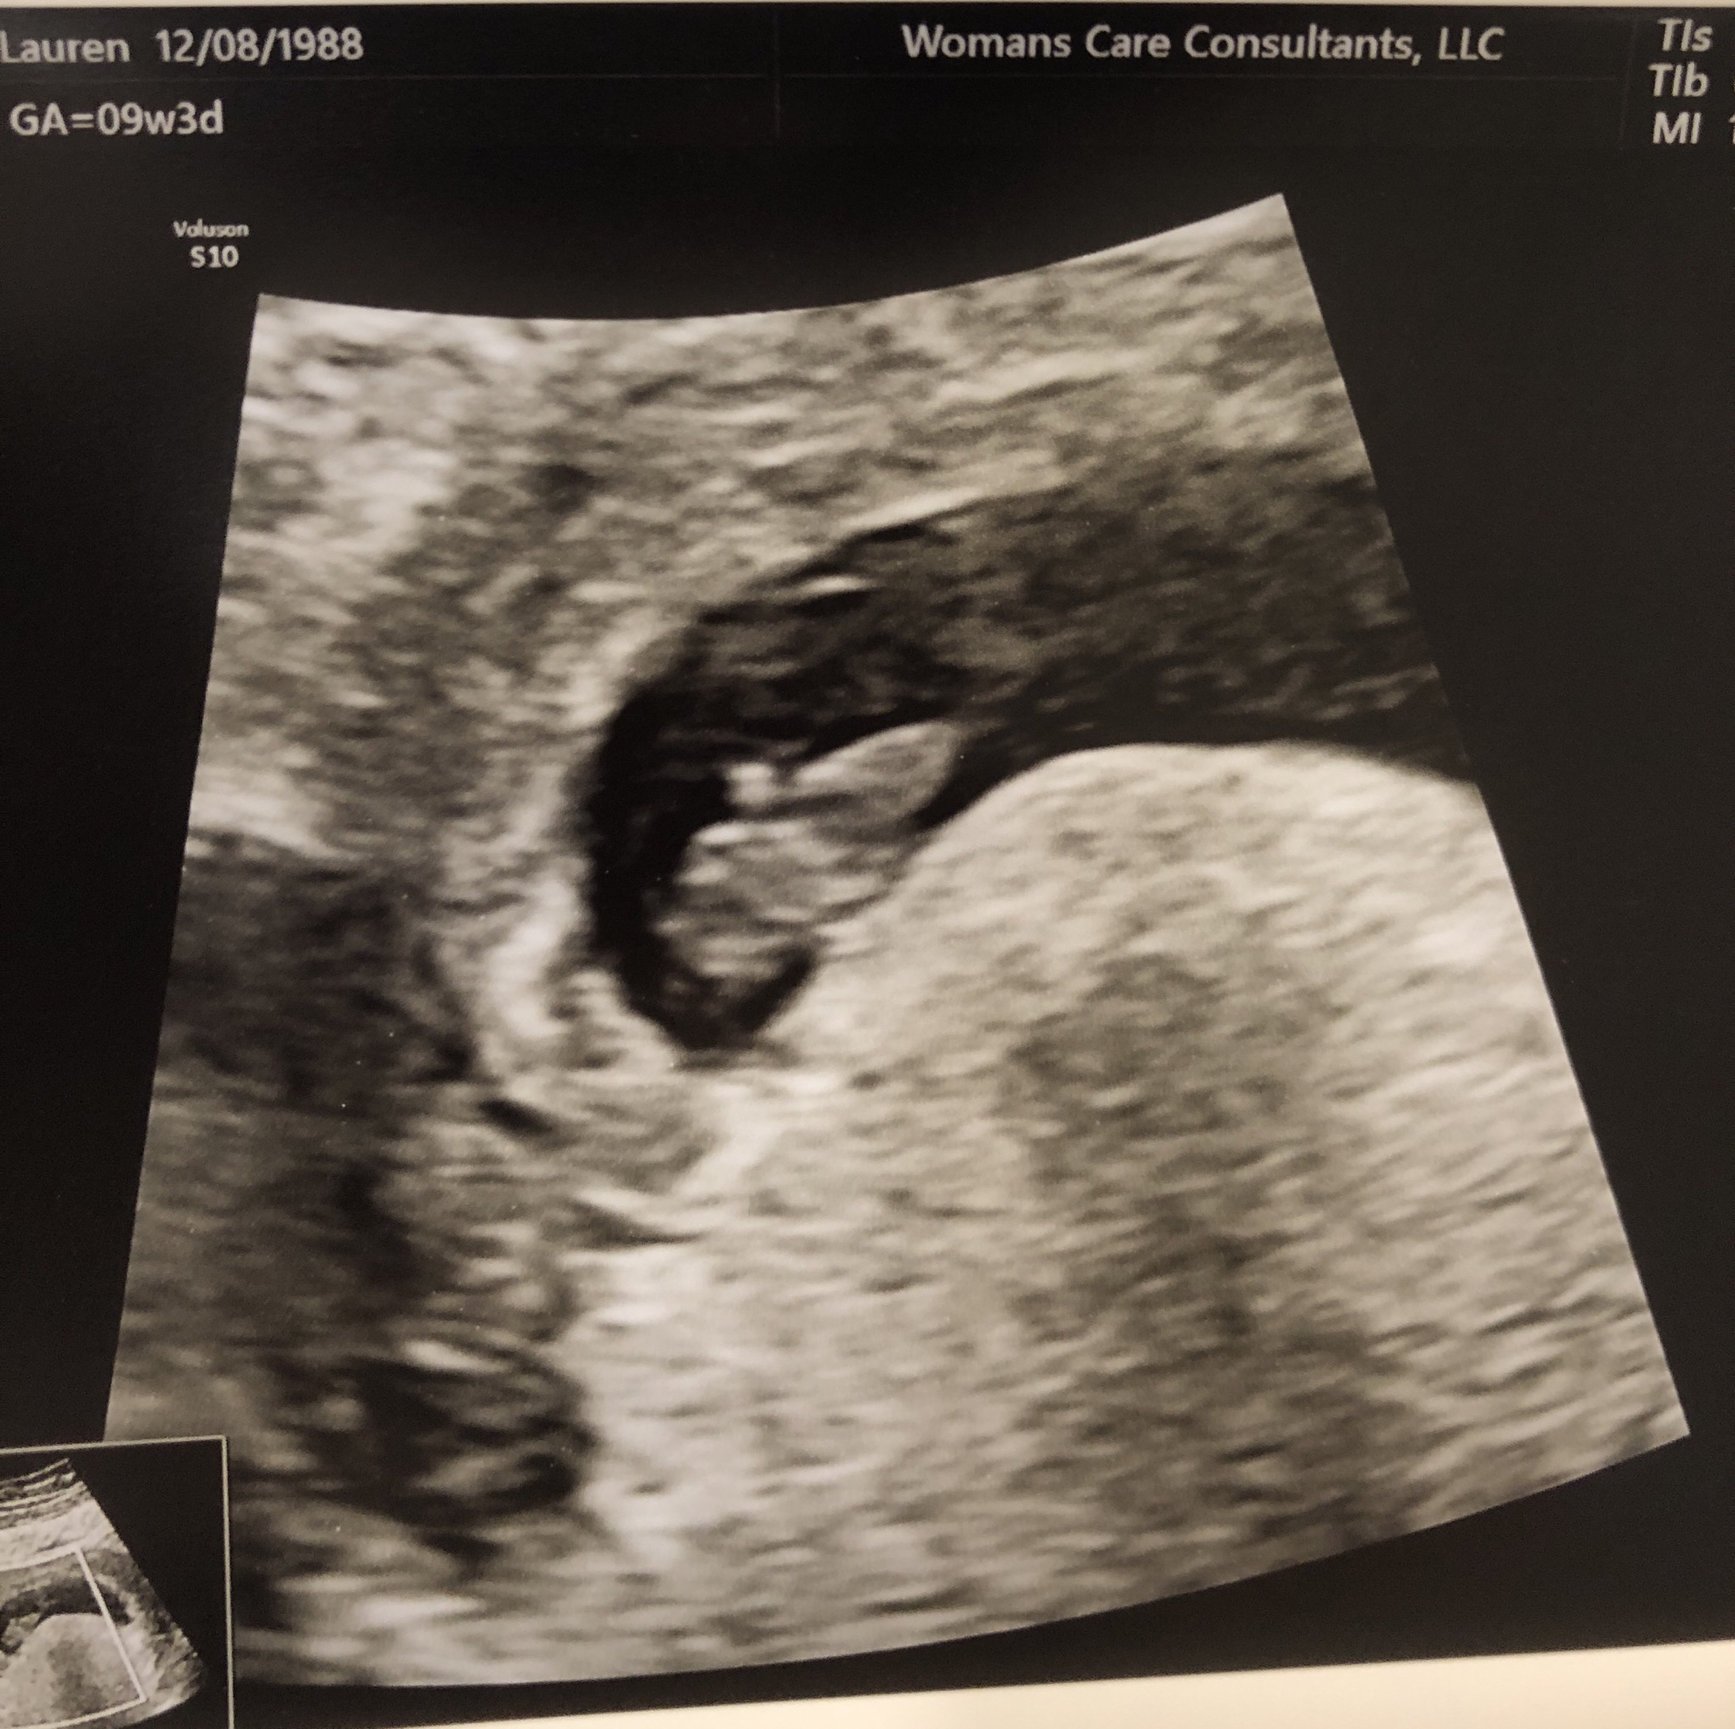

I'm a double loss momma, so my specialist is monitoring me closely. All of my betas have been increasing well and I had my first ultrasound today. The dr dated me at 6w+2 (I thought I was 6w+5, but maybe little one took a few days to implant.)

got to hear the heartbeat today too! It was such a gift to get to hear it. Heart rate was 122 and so far everything looks good. He said if I can make it two more weeks my loss chance goes down significantly. Next ultrasound at 8 weeks.

Our little one! Strong heartbeat at 121! So happy and relieved to see our sweet little baby!